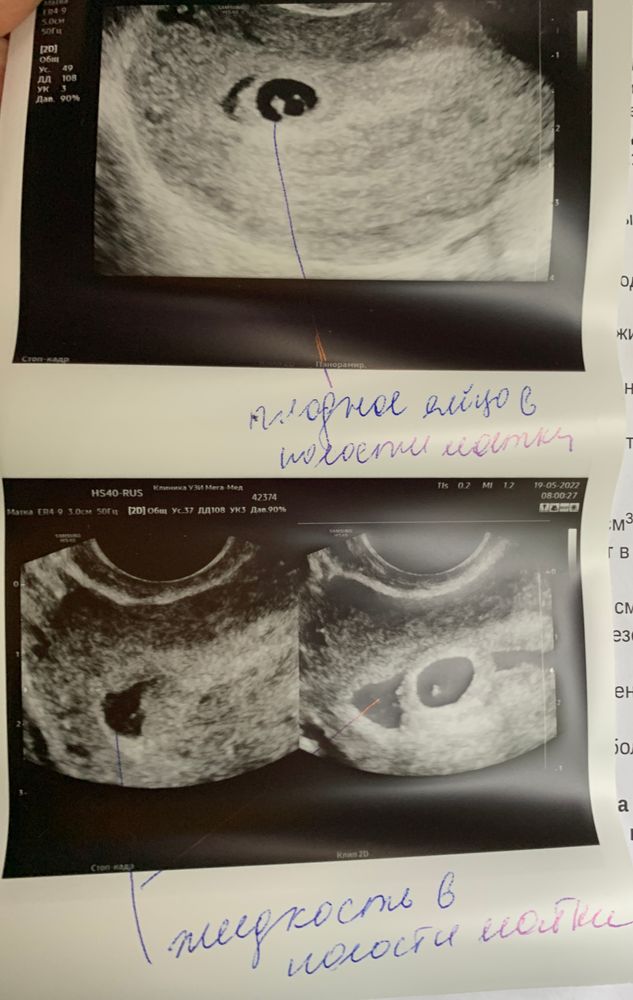

УЗИ результаты: что такое признаки беременности малого срока и неоднородное жидкостное содержимое в полости матки?

Всем добрый день! Сегодня была на УЗИ в частном центре. Заключение: Признаки беременности малого срока. ПРИЗНАКИ НЕОДНОРОДНОГО ЖИДКОСТНОГО СОДЕРЖИМОГО В ПОЛОСТИ МАТКИ. Что это вообще такое? УЗИст ничего не сказала конкретного, просто «пока всё нормально». Мне 30 лет. В декабре первая беременность закончилась ЗБ. После этого проходила обследование, всё было хорошо, гинеколог разрешила планировать беременность.